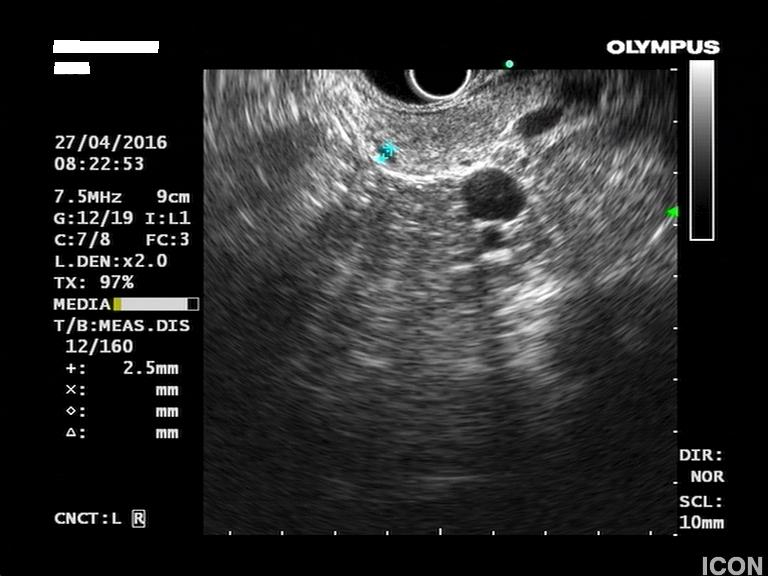

Η κύστη είχε επικοινωνία με κλάδο του παγκρεατικού πόρου, ενώ ο μείζων παγκρεατικός πόρος ήταν φυσιολογικής διαμέτρου σε όλη την πορεία του. Επίσης, διαπιστώθηκε δεύτερη κύστη διαμέτρου 2,5χιλ στο σώμα του παγκρέατος που δεν είχε απεικονιστεί στην MRI.

Δεύτερη μικρότερη κύστη στο σώμα του παγκρέατος